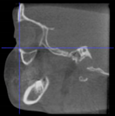

Three points determined the Acta plane: O, F right (FR), and F left (FL) (Table 2). Point O is the midpoint between the most craniodorsal point of the dorsum Sella and the most posterior dorsal point of the Basion in the midsagittal plane (Figure 1). Both points F are a result of the intersection between two lines: the line that connects the most inferior points of the lower orbital margins, right and left, and a line perpendicular to this line that runs through the most external points of the orbital margins, right and left (Figure 2). The new transverse reference plane, the Acta plane (Figure 2), is created by connecting the O-point (Figure 1) with FR and FL (Figure 2).

Figure 2.

(A) Construction of the F-points (right and left), frontal view. The F-points are originated from the intersection between the line connecting points A (the most inferior point of the lower orbit) and the perpendicular line to it that passes through points B (most external/lateral point of the Orbita). (B) Transverse view of the ACTA plane.